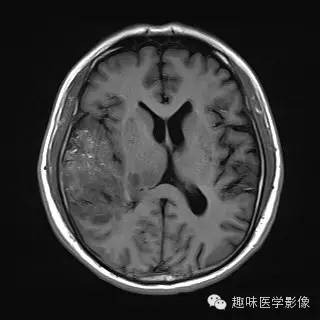

【病例】少突胶质细胞瘤1例MR影像表现

性别:男年龄:48岁 间断性四肢抽搐9月余,头晕伴肢体无力1月余

[影像表现]

右侧颞顶叶、丘脑可见大片不规则异常信号灶,局部脑回肿胀,大小约45×75mm,T1WI呈混杂低信号,内可见多发条状高信号,中央可见更低信号灶,T2WI/FLAIR呈混杂稍高信号,内可见点状低信号,DWI呈混杂高信号,未见明显占位效应,增强后呈多发不规则花环状明显强化灶,内可见多发点状小血管影。

少突胶质细胞瘤,WHOⅡ级。

少突胶质细胞瘤为分化良好、生长缓慢但呈浸润性的肿瘤,典型者累及皮层和皮层下白质,20%-50%有侵袭性(间变性少突胶质瘤)。最佳诊断征象:部分钙化 中年人的皮层肿块,可以侵蚀并使颅骨膨胀。CT平扫为低/等密度,大部分钙化,可有出血和囊变,增强CT表现多样,从无增强到明显增强。MRI常不均匀,T1WI上相对于皮层为低/等信号,T2WI为高信号;除间变外,出血、坏死少见,边界清楚,伴轻微水肿,50%强化。